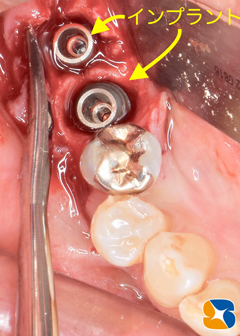

ノーベルバイオケア社製のアクティブ直径5㎜、長さ11.5㎜を移植完了。

インプラント移植直後の状態。周囲の骨は抜歯の影響で、スカスカ空洞があります。

吸収性の人工骨に患者様御自身の血液で製作したコラーゲンとフィブリンの塊を混ぜて、不足している

骨の部分に添加しました。

コラーゲンの塊をシート状に圧縮して確実な骨の再生を促します。

当院でインプラント施術を受けられる方には、一連の作業は無料でおこなっています。